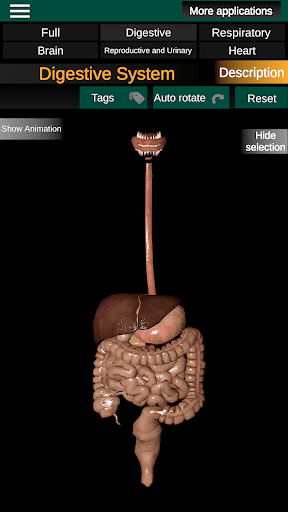

* Sistem pencernaan, termasuk lambung, usus kecil, usus besar, dan animasi sistem ini.